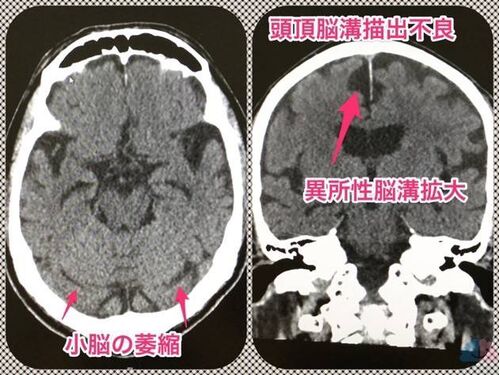

正常圧水頭症を合併している混合病態で気をつけていること。

複数の病態が共存している場合、何から手を付けるかは重要である。 緊急で改善すべき点があれば、そこから取り組む。さし当たっての緊急性が無ければ、早めの是正が望ましい点を見つけて、そこに取り組むようにしている。